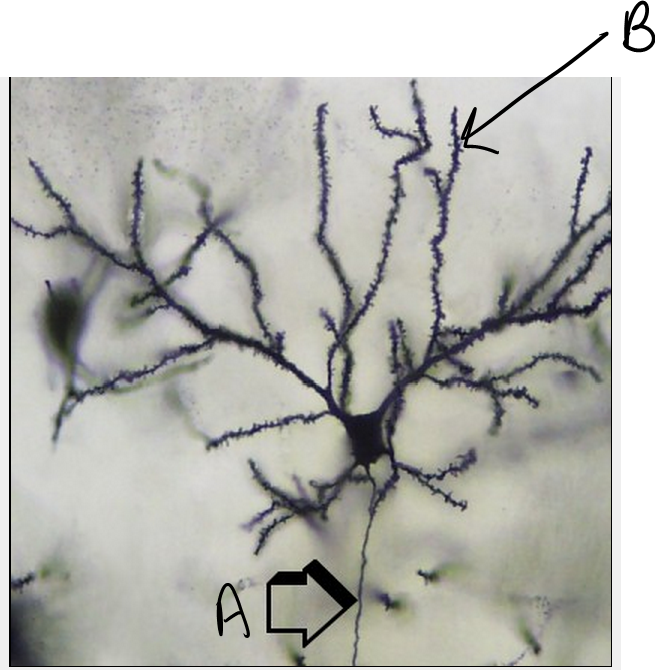

1

Q

What are the structures labed A and B?

A

A= Axon

B=Dendrite